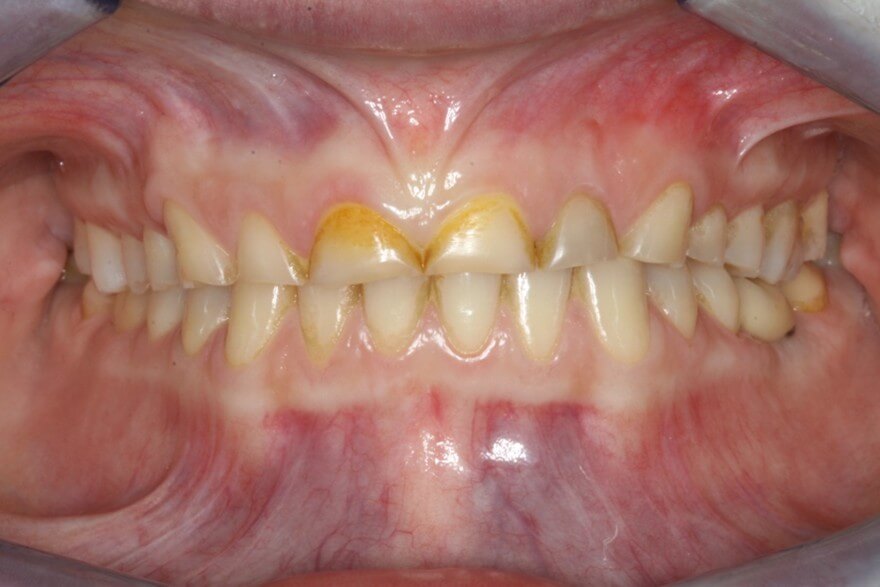

- Τα δόντια έχουν υποστεί έντονη φθορά ή έχουν χαθεί λόγω εκτεταμένων τερηδόνων, περιοδοντικής νόσου ή τραύματος.

- Τα δόντια έχουν φθαρεί και έχουν χάσει τα χαρακτηριστικά τους (σχήμα, μέγεθος) λόγω διάβρωσης από οξέα (τρόφιμα, ποτά, γαστροοισοφαγική παλινδρόμηση) ή χρόνιου βρυγμού.

Κλινικές Περιπτώσεις